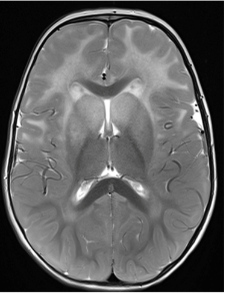

A radiologic diagnosis of Alexander disease is based on the presence of 4 out of 5 MRI features, which are most commonly observed in people with earlier age of onset (ie, infants and young children)1,15,16:

- Frontally predominant white matter changes1

- Periventricular rim abnormalities (eg, high T1-weighted signal and low T2-weighted signal)1

- Abnormalities of the basal ganglia and thalami1

- Brainstem abnormalities1

- Contrast enhancement of 1 or more of the following structures: ventricular lining,

frontal white matter, optic chiasm, basal ganglia, thalamus, fornix, dentate nucleus,

and brainstem1